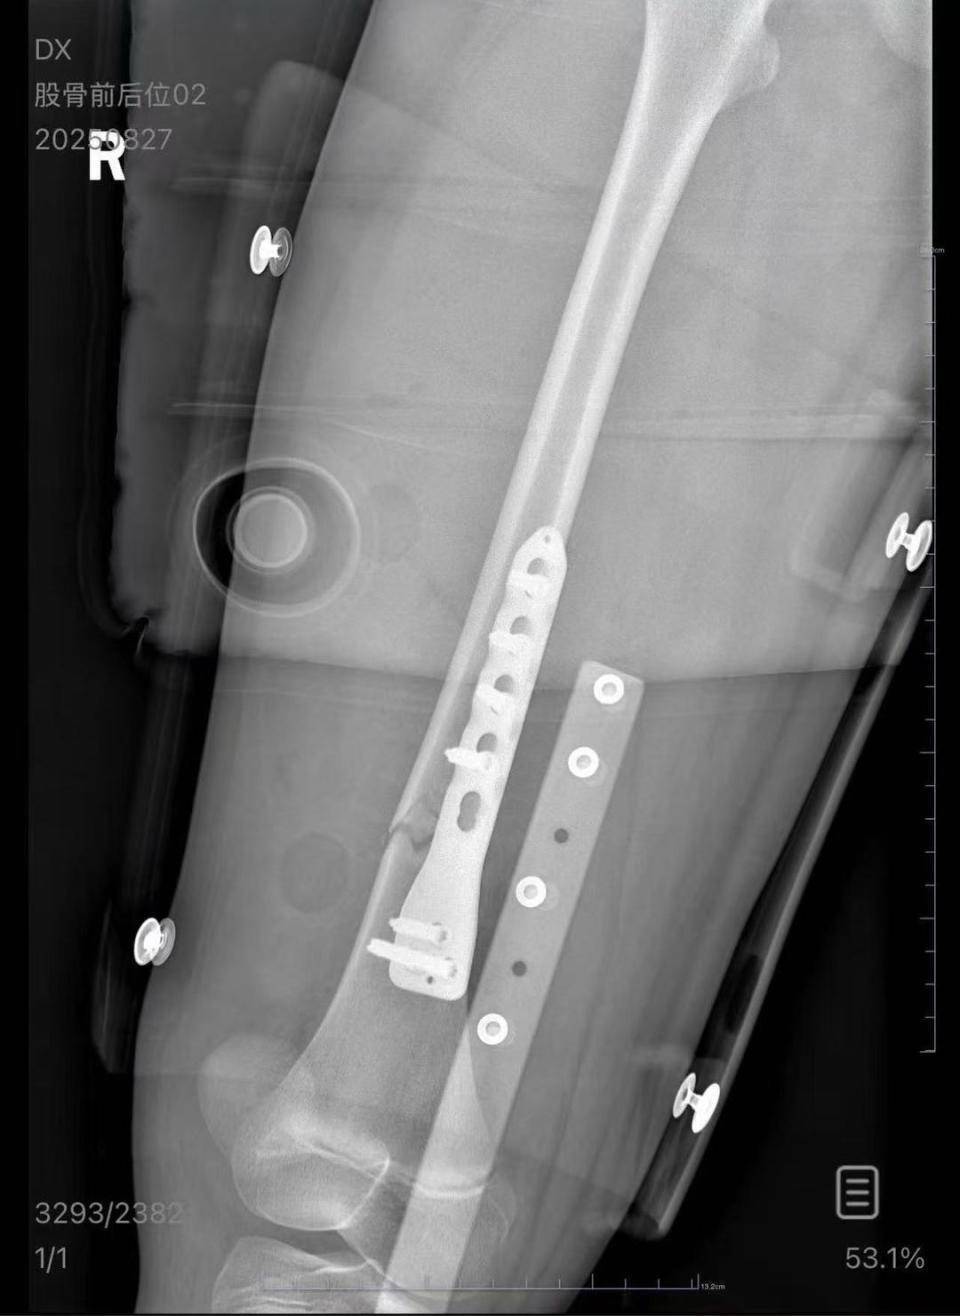

朱女士向记者出示的医院病历显示,8月24日凌晨,朱女士的女儿到医院就诊。医院诊断朱女士的女儿右股骨骨折,需要住院进一步治疗。

朱女士女儿手术后拍的X光片 受访者供图